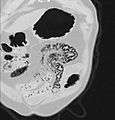

Pneumatosis intestinalis in computed tomography with intestinal ischemia. Lung window for better representation of the gas deposits in the intestinal walls.- Upright AP radiograph showing gas in the wall of the small bowel in the left upper quadrant indicative of pneumatosis intestinalis.

- Coronal reformatted MDCT image showing extensive pneumatosis intestinalis in the left upper quadrant small bowel. The pneumatosis is more cystic and nodular in the small bowel in the midline and the right of midline. This patient had a relatively benign presentation without bowel ischemia and was treated conservatively.